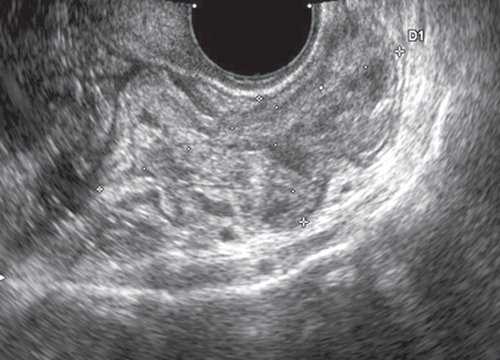

При УЗИ, проводимом по общепринятой методике полостным датчиком частотой 7 МГц, визуализировалась культя шейки матки с ровными четкими контурами размером 5,2х5,3х3,7 см. Структура ткани неоднородная, с наличием кист размером от 0,4х0,4 до 0,7х1 см. Цервикальный канал не расширен. Эндоцервикс не утолщен. Правый яичник расположен типично, его размер 3,5х1,9х3,5 см. Контуры четкие, ровные. В структуре определяются два аваскулярных жидкостных образования размером до 1 см с тонкими стенками и однородным содержимым. Левый яичник расположен типично, его размер 2,8х1,6х2,4 см. Контуры четкие, ровные. Структура умеренно неоднородная, фолликулы не определяются. Жидкости в позадиматочном пространстве не выявлено.

К задней стенке культи шейки матки прилежит участок прямой кишки толщиной до 2,9 см на протяжении до 7,4 см. Стенка кишки неравномерно утолщена до 0,5-0,6 см, пониженной эхогенности, дифференцировать слои стенки не представляется возможным. При ультразвуковой ангиографии на измененном участке определяется выраженная васкуляризация с наличием сосудов с артериальным типом спектра (Vmax 14,4 см/с, RI 0,74). Перистальтика кишечника в данном сегменте отсутствует, внутренний просвет не дифференцируется. Слева от описываемого участка кишечника в межкишечном пространстве определяется гипоэхогенное образование с четкими ровными контурами, неоднородной структуры, размером 2,6х1,9х2,3 см. При ультразвуковой ангиографии в нем лоцируются множественные деформированные сосуды (рис. 1, а, б, в).

а) В-режим.

В полости малого таза, кзади от культи матки, определяется участок кишечника размером до 6,8х2,9х7,4 см с утолщенной до 0,5-0,6 см стенкой сниженной эхогенности. Перистальтика кишечника в данной проекции отсутствует, внутренний просвет дифференцируется нечетко. Содержимое кишечника практически не определяется, просвет сомкнут.